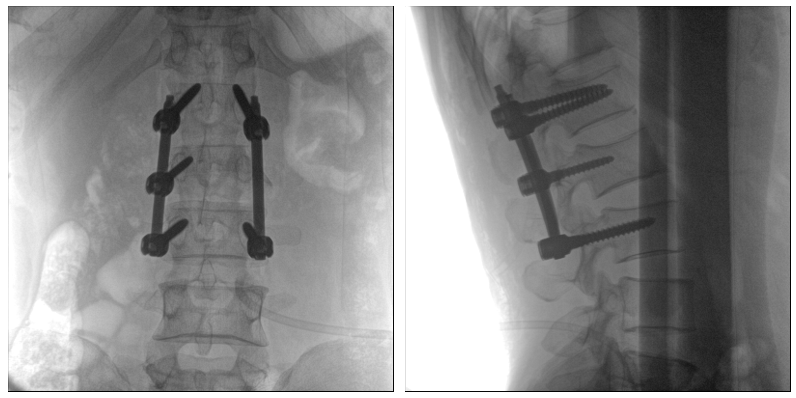

術(shù)中二維影像

從圖中可以看到二維影像能夠提供目標(biāo)區(qū)域在某一個平面的重疊影像,雖然因為人體不同組織的密度差異,使得圖像具有較為豐富的信息量,但組織間的相互重疊還是會出現(xiàn),諸如空間位置等眾多信息在影像中遺失或不可辨認(rèn)的情況,影響了醫(yī)生對信息的收集與應(yīng)用。